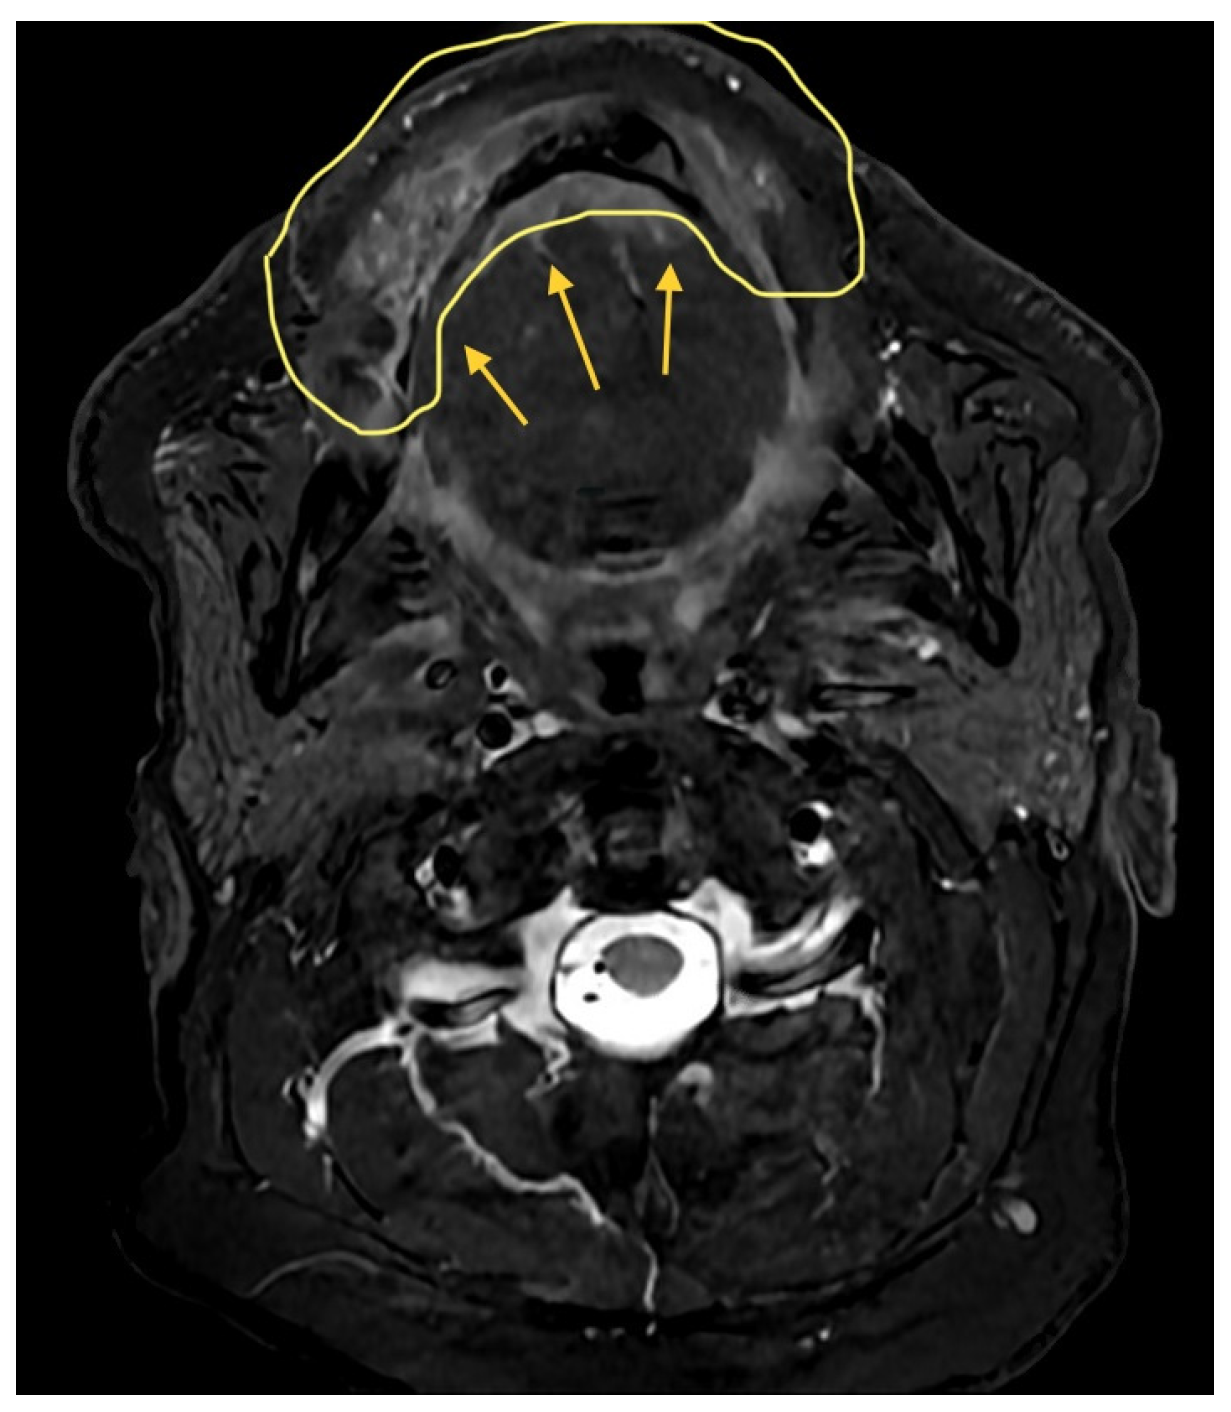

3.2. Case 2

A 37-year-old female underwent extended hemiglossectomy with ipsilateral neck dissection in April 2024 for a pT3N1M0 (DOI 17mm) moderately differentiated squamous cell carcinoma. Immediate reconstruction was undertaken using a modified non-dominant radial forearm fasciocutaneous free flap using the Mitaka Hawksight platform (Mitaka USA Inc., Wheat Ridge, CO, USA) for microsurgery (Figure 4, Figure 5, Figure 6 and Figure 7).

Adequate illumination and visual clarity facilitated successful microvascular anastomoses without reverting to the OM.

Figure 4. Case 2—Tongue Tumor surgical marking.